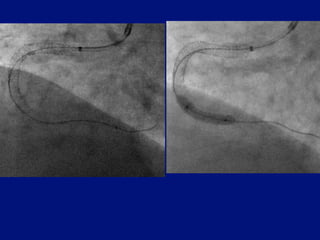

Severe proximal and distal disease

Severe proximal

disease causes

pressure damping

prevents coronary

intubation

Distal disease cannot

be reached

Severe proximal anddistal disease Severe proximal disease causes pressure damping prevents coronary intubation Distal disease cannot be reached